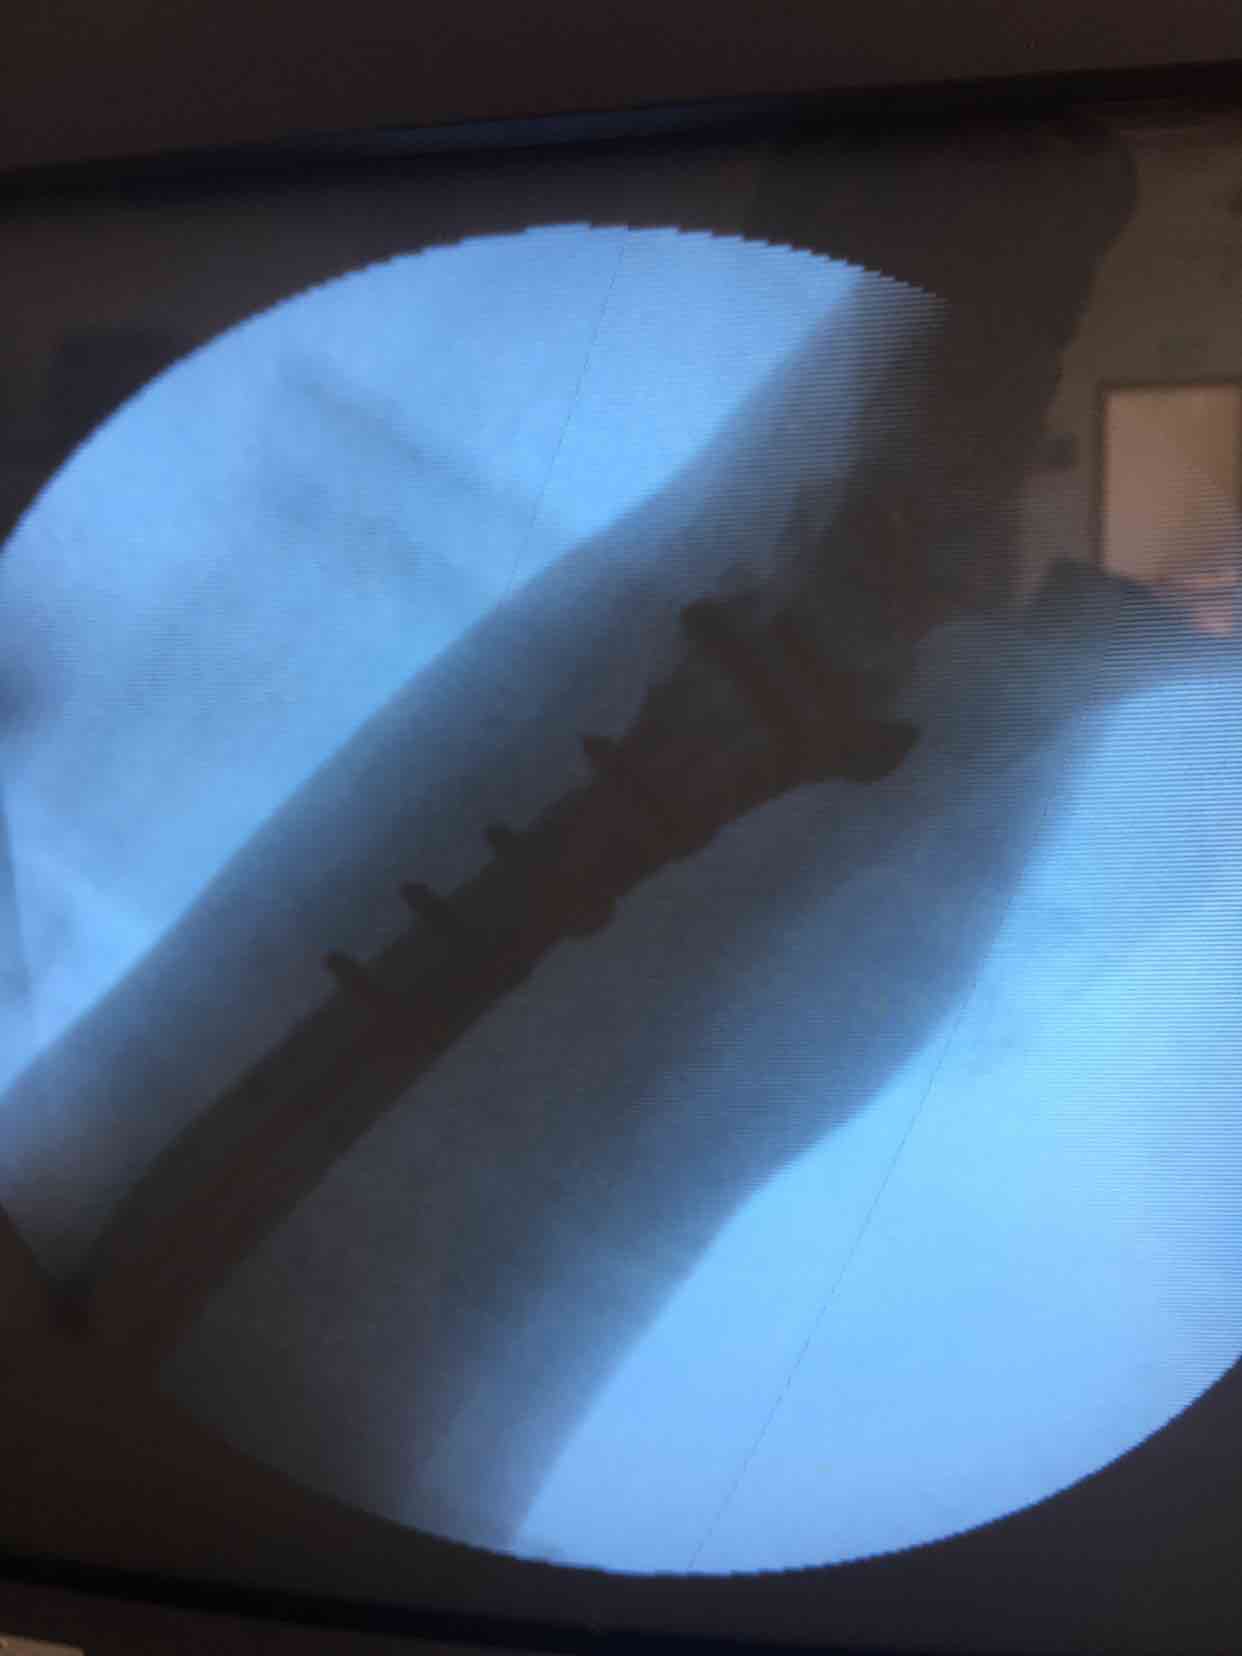

诊断尺桡骨远端粉碎性骨折在臂丛麻醉下行切复内固定术,术中克氏针临时固定,维持复位,术后石膏托固定,抗炎,消肿等处理。